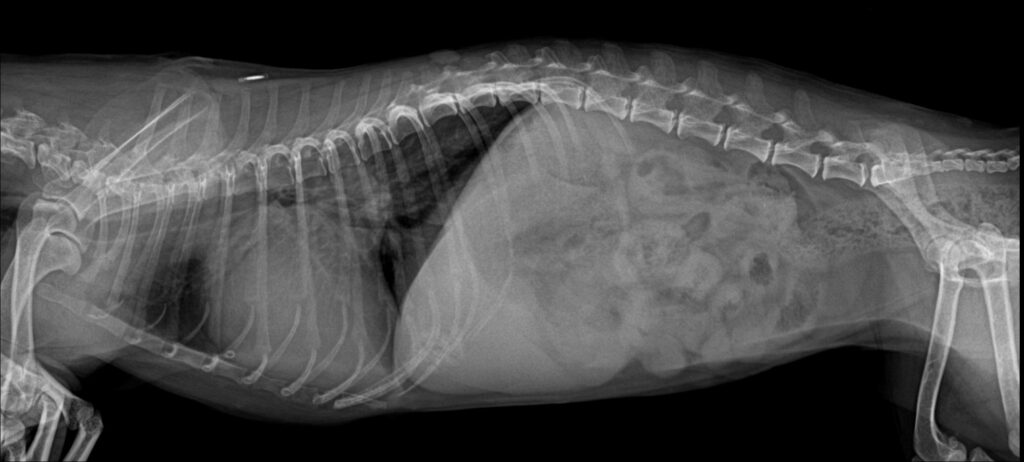

흉부 방사선 검사

흉부 방사선검사 / 출처: 미래동물의료센터

흉부 X-ray 검사 결과, 우측 후엽 폐 영역에서 뚜렷한 폐침윤 소견이 확인되었고 전반적인 심비대 소견도 함께 관찰되었습니다.

이러한 임상 증상과 영상 소견을 종합하여 심인성 폐수종을 우선적으로 의심하되, 비심인성 폐수종 가능성도 함께 고려한 상태로 진단하였습니다.